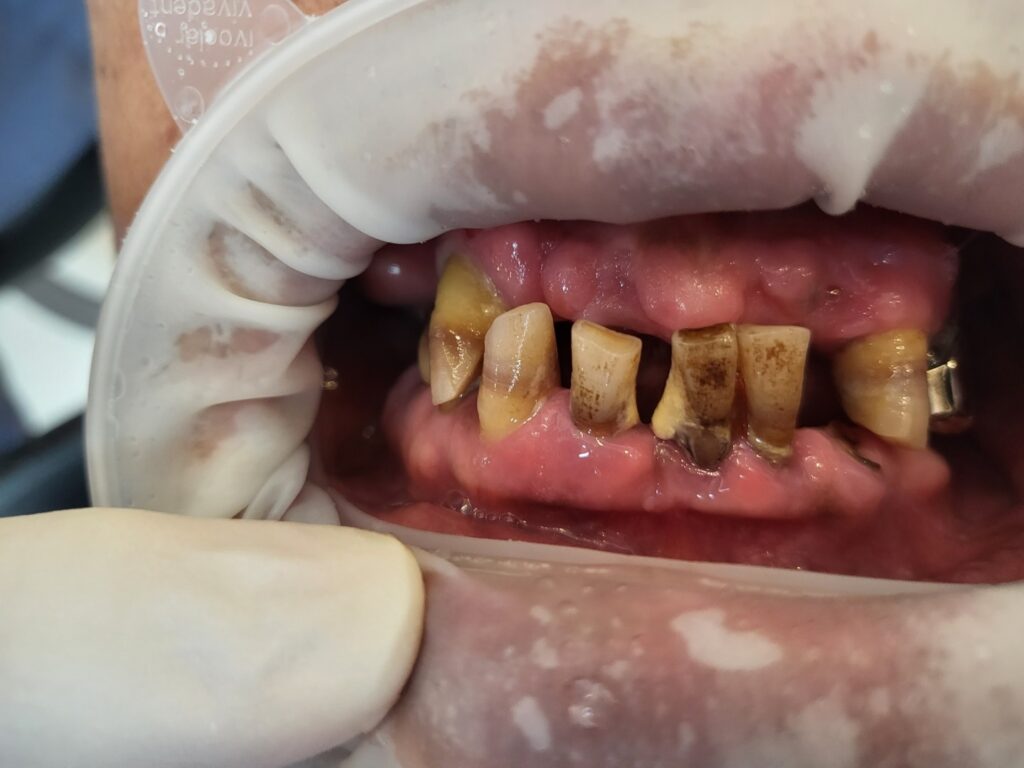

오늘 소개해 드릴 사례는 50대 남성으로 여러개의 치아가 빠졌는데 치아를 해 넣지 않고 그 상태에서 방치하여 치아들이 모두 망가진 경우입니다.

없어진 치아를 제때 해 넣지 않으면 이렇게 기본적인 위아래턱의 높이(고경)가 변화합니다. 아래턱와 위턱의 관계는 치아가 어떻게 만나는가에 의해 정해지기 때문입니다

치아마모와 고경상실 만성치주염

없는 치아를 대신해서 남은 치아들이 식사할 때 억지로 사용되면서 고경이 점점 무너지고 치아도 마모가 급격하게 진행되었고, 거기에 위생관리도 되지 않아서 치주도 좋지 않았습니다.

결국 살릴만한 치아가 전혀 없어서 모두 발치를 결정하고 전체임플란트를 계획했습니다. 다행이 뼈상태는 양호하신 편이라 즉시하중을 시도하기로 했습니다.